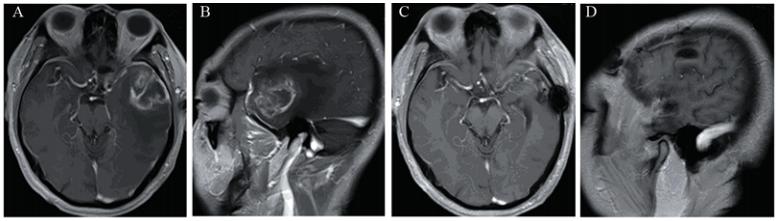

四组脑胶质瘤患者存活率 及中位生存时间见表1,生存曲线见图4。RT 组与 TMZ + RT 组和ACNU + RT 组的生存曲线比较, 差异有统计学意义(χL2=8.313和8.825,P=0.003和 0.012),即ACNU + RT组和TMZ + RT组的中位生 存时间长于RT 组;ACNU + RT 组和TMZ + RT组 生存曲线差异无统计学意义(χL2=0.047,P=0.915), 即ACNU + RT 组和TMZ + RT组生存时间差 异无统计学意义。ACNU+TMZ+RT分别与 ACNU+RT、TMZ+RT的生存曲线比较差异有统计 学意义(χL2=21.045和22.385,P=0.043和0.045),即 ACNU+TMZ+RT中位生存时间长于ACNU + RT 组 和TMZ + RT 组。

表1 四组脑胶质瘤患者生存时间比较 Table 1 Comparison of survival time of glioma patients in four groups |

| 图4 四组脑胶质瘤患者生存曲线图Figure 4 Survival curves of glioma patients in four groups |